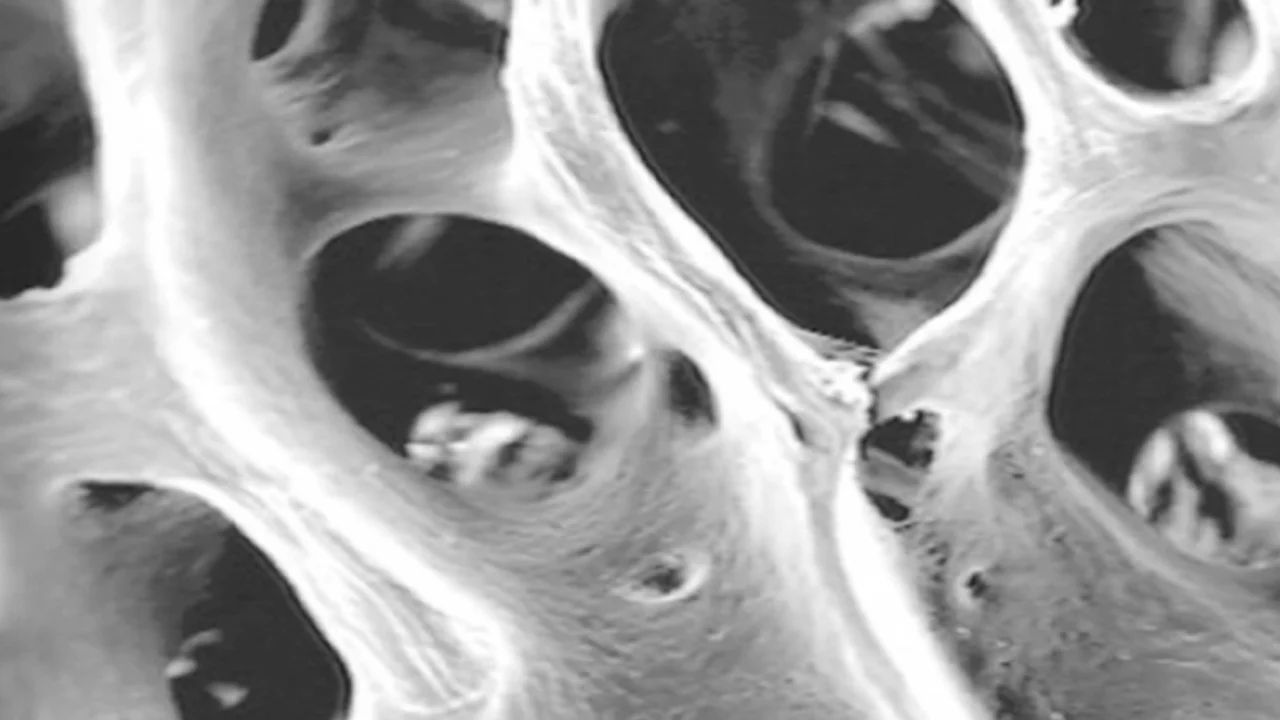

Enzymatické čištění zachovává trojrozměrnou strukturu kolagenových vláken. To je klíčové pro tzv. osteokondukci.

Vysoká vaskularizace: Studie prokázaly, že zachovaný kolagen v materiálech Osteoxenon® působí jako „lešení“, které aktivně přitahuje krevní cévy a kostní buňky (osteoblasty).

Stabilita sraženiny: Kolagen přirozeně stabilizuje krevní sraženinu v místě defektu, což je první a nejdůležitější krok k úspěšnému zhojení nové kosti.